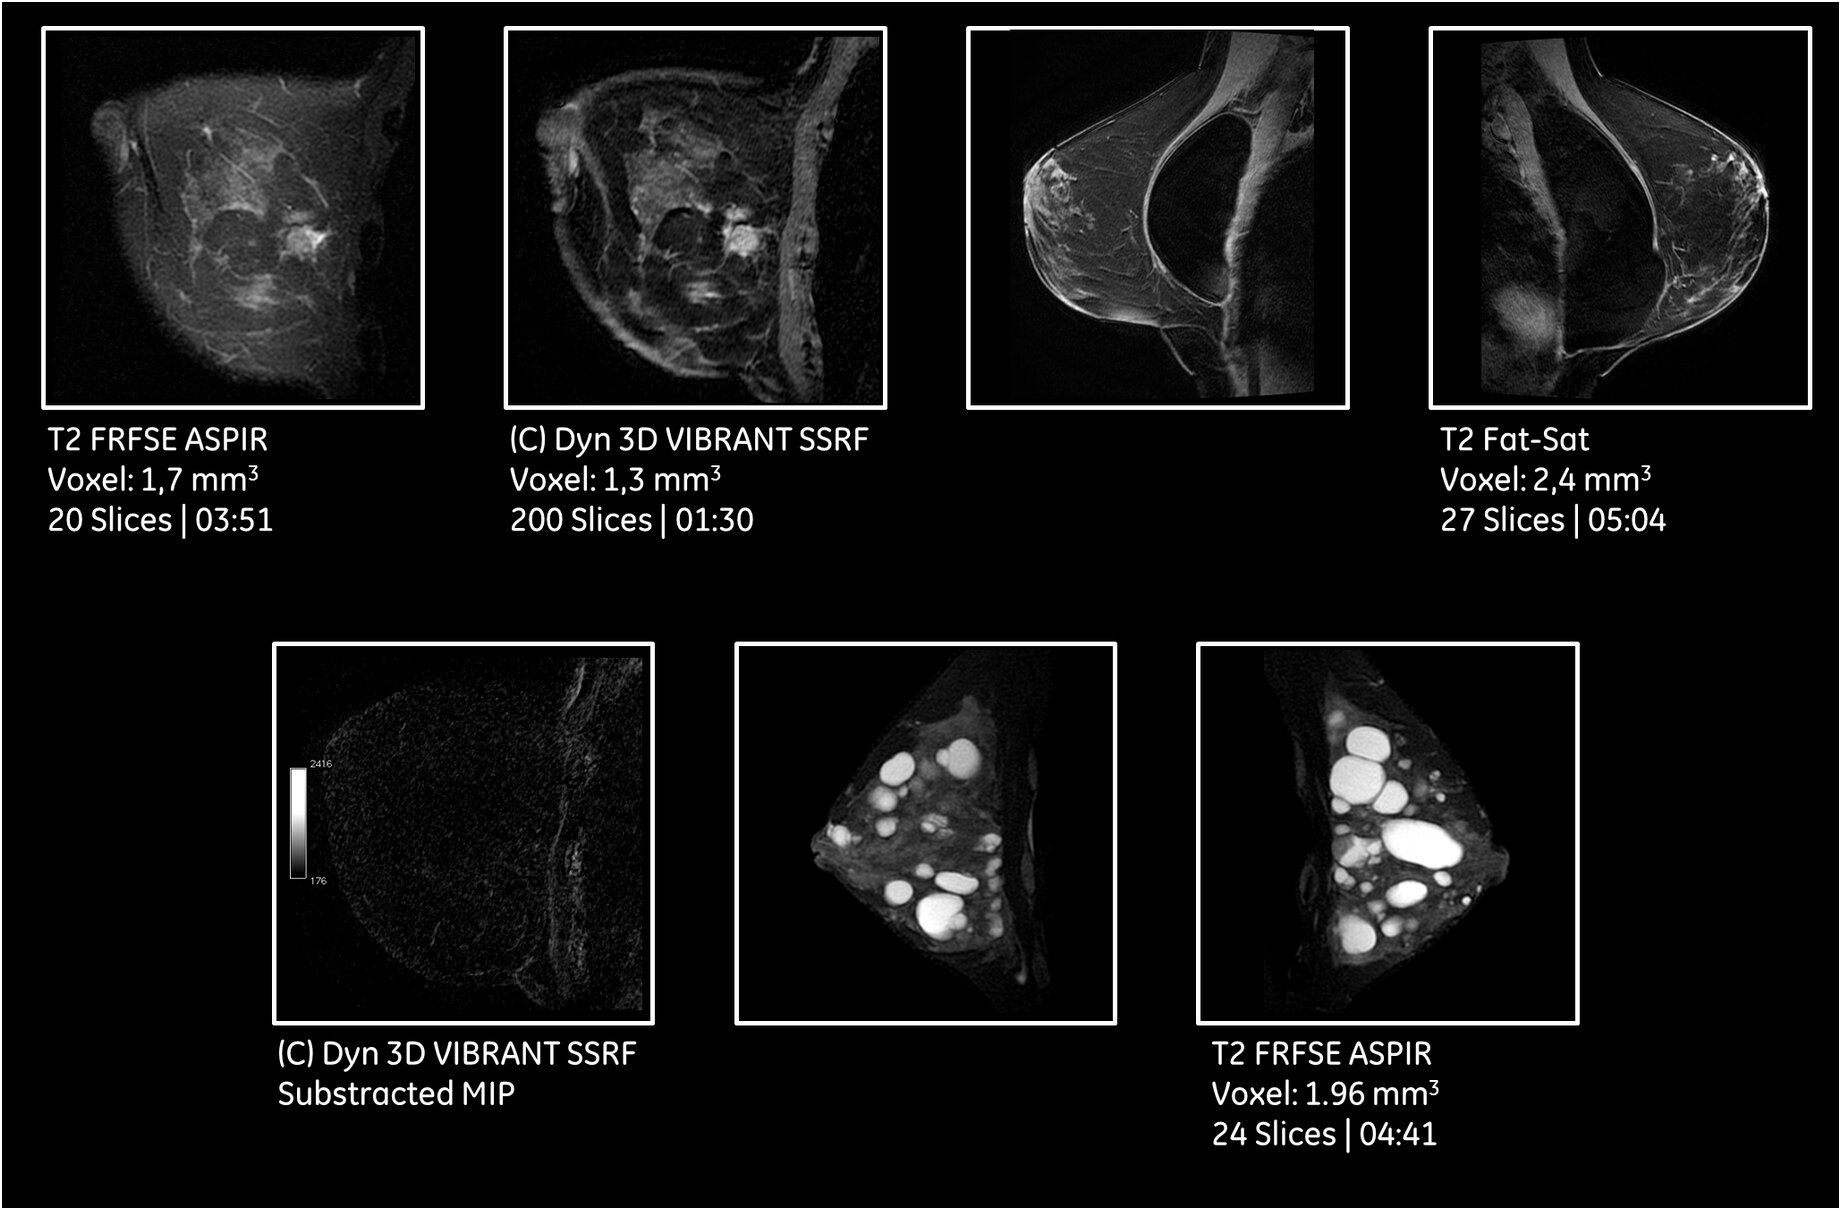

With its free-breathing imaging applications and advanced motion correction software, SIGNA™ Pioneer will compensate for patient movement and allow complete free-breathing body imaging. This includes dynamic contrast enhanced MR imaging, improving dramatically

patient experience but also image quality in very challenging situations.